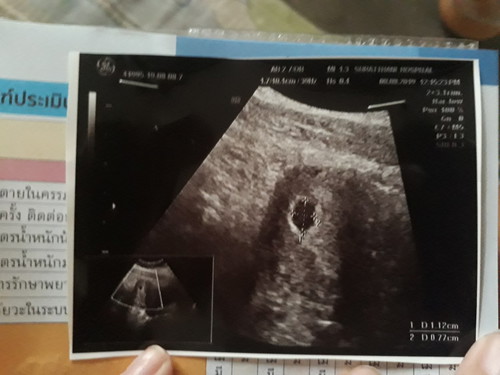

พอดีท้องได้ตอนนี้ 8 สัปดาห์ ตอน 6 สัปดาห์ไปฝากท้องคุณหมอให้ซาวเจอถุงการตั้งครรภ์ค่ะ หลังจากนั้น5 วัน คุณหมอซาวให้ใหม่ทางช่องคลอด บอกไม่เจอตัวเด็กจะให้ขูดมดลูก แต่พยาบาลบอกให้ซาวหน้าท้องอีกทีก็ยังเห็นถุงตั้งครรภ์เหมือนครั้งแรก และนัดอีก3 สัปดาห์ มาซาวใหม่เพื่อดูว่าจะเห็นตัวไหม แม่เครียดมากค่ะ ท้องนี้ท้องที่2 ท้องแรกซาวตอน12สัปดาห์ เห็นชัดค่ะ เลยอยากสอบถามว่ามีใครเป็นแบบนี้ไหมค่ะ